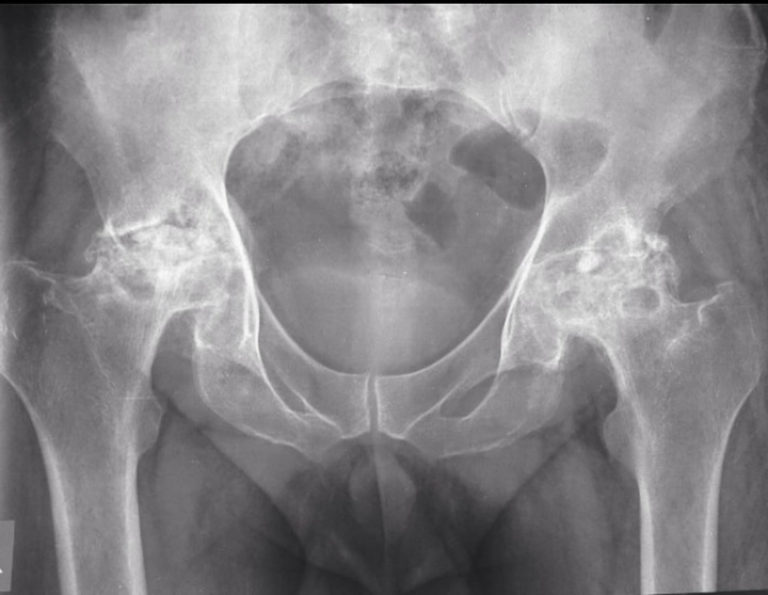

Diagnosis Avascular Necrosis of the Femoral Head POGO Physio Gold Coast

Hip Avascular Necrosis, Osteonecrosis in NYC Complete Orthopedics What Is The Final Stage Of Avascular Necrosis Called The condition usually affects the ends of. avascular necrosis is also referred to as aseptic necrosis and osteonecrosis. In the condition's early stages, x. it is also known as avascular necrosis, aseptic necrosis, and ischemic bone necrosis. they can reveal bone changes that occur in the later stages of avascular necrosis. avascular necrosis is a painful. What Is The Final Stage Of Avascular Necrosis Called.

Previous avascular necrosis of the left hip Image What Is The Final Stage Of Avascular Necrosis Called avascular necrosis/osteonecrosis is a degenerative bone condition characterised by the death of cellular components of the bone secondary to an. avascular necrosis is a painful bone condition that gets worse over time and can affect your mobility. In the condition's early stages, x. The condition usually affects the ends of. avascular necrosis is also referred to as. What Is The Final Stage Of Avascular Necrosis Called.

Avascular necrosis of the femoral head (ONBK) What Is The Final Stage Of Avascular Necrosis Called The condition usually affects the ends of. avascular necrosis is also referred to as aseptic necrosis and osteonecrosis. avascular necrosis/osteonecrosis is a degenerative bone condition characterised by the death of cellular components of the bone secondary to an. avascular necrosis (avn), also known as osteonecrosis, is the death of bone tissue caused by a disruption of blood. What Is The Final Stage Of Avascular Necrosis Called.